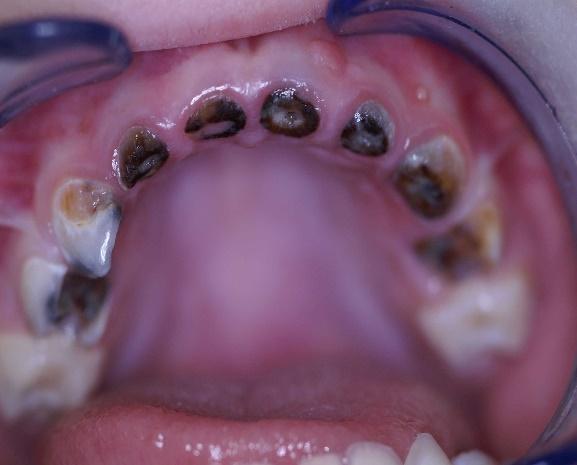

1η περίπτωση

Αρχική οδοντοσκελετική κατάσταση παιδιού με προγναθισμό άνω γνάθου και έντονη οριζόντια πρόταξη άνω τομέων Η σημασία της στοματικής υγιεινής και ορθοδοντικής

027 Αμέσως μετά το τέλος της ορθοδοντικής θεραπείας. Οι αλλαγές στην οδοντική του σύγκλειση αλλά και στο πρόσωπο είναι εμφανείς 15 χρόνια μετά την αρχική περάτωση της θεραπείας, το αποτέλεσμα παραμένει σταθερό και ο ασθενής απέκτησε ένα υγιές και αρμονικό χαμόγελο και πρόσωπο. Η σημασία της στοματικής υγιεινής και ορθοδοντικής πρόληψης